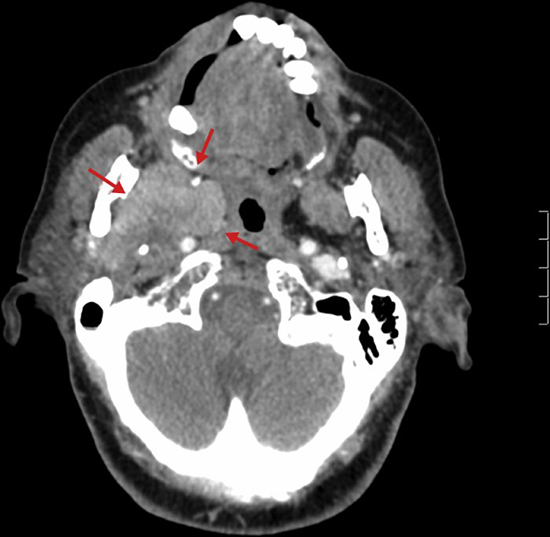

De igual forma se podría utilizar estudios imagenológicos más sofisticados para lograr un correcto diagnóstico, como lo son la tomografía computarizada (TC) la cual debe ser indicada en pacientes en los que se sospeche la presencia de una lesión de tipo infecciosa o la presencia de una neoplasia. Un sustito para la TC es la resonancia magnética (RM- MRI) según la preferencia del clínico.